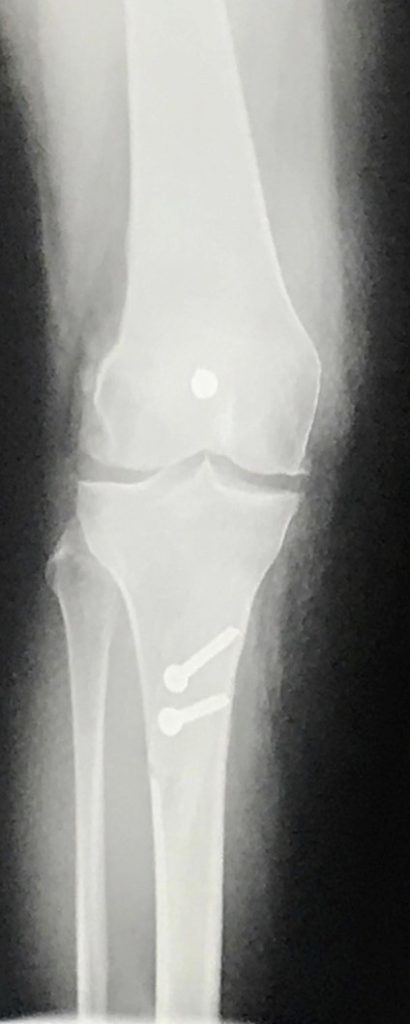

In the summer of 2019, Dr. Williams accepted the challenge and performed a tibial tubercle osteotomy (TTO), implanted several cadaver cartilage transplants on my patella and tibia, and experimentally injected stem cells and capillaries into my right knee. The procedure and recovery were intense and life changing. Within 6 weeks my knee was stable and mobile, and within 3 months I was able to RUN through a WET, LEAFY parking lot at NIGHT. After suffering from 25 years of knee instability and arthritic pain, running on an uneven surface at night is nothing short of a miracle. Also, as a long-distance open water swimmer, being able to swim again without my knee dislocating healed my soul. It was as if my knee was 16 again!